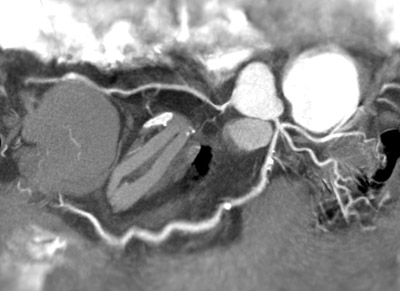

The procedure to image the heart and see the details of the vascular system that feeds the heart wall with oxygenated blood is technically demanding. This procedure, known as Cardiovascular Computed Tomography Angiography or CCTA, is an emerging application. It can evaluate the presence of occlusive disease and the efficacy of subsequent interventions in coronary vasculature. There are challenges inherent in the imaging of the coronary arteries associated with the motion of the heart. The challenge in achieving high image quality and visibility of sub-centimeter coronary vessels is to time the exposure to the most quiet moment within the cardiac (heart beat) cycle. The success of the CCTA examination of the coronary arteries is dependent upon the optimization of a number of enabling technologies, most importantly the ability to achieve higher rotation speeds.

Image courtesy of Washington Hospital Center

Image of the coronary arteries in a patient with a heart rate of 80 ± 6 bpm.

Images were acquired in end-systolic coronary rest phase using a 0.27 second rotation time.